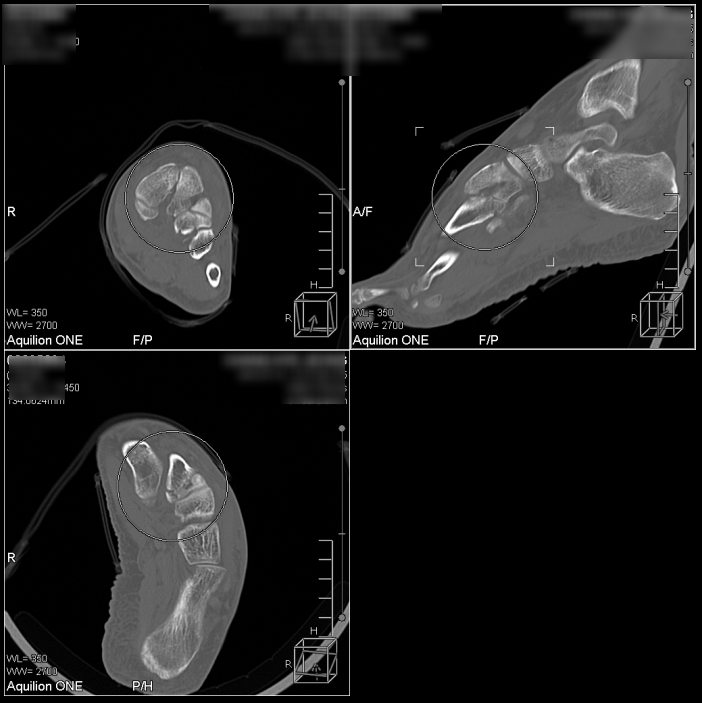

설상골(cuneiform bone)부터

2/3/4 중족골까지,

무려 4군데 다발성 골절로 진단되었습니다.

영상의학과에 대학병원급 장비인 640CT가 있어서

작은 실금이나 미세골절, 견열골절들을 잘 잡아내십니다.

만약 골절을 모른채, 고정하지 않고 평소와 같이 생활하셨다면 뼈가 잘 붙지 않거나 골절 부위가 벌어져 빨리 낫지 않으셨을 겁니다.

다행스럽게도 본원에서 골절을 의심하여 영상의학과로 전원하여 신속하게 진단이 이루어졌고,

정형외과에서 정복이나 수술이 필요한 상태가 아니니 붓기 빠질 때까지는 반깁스를 먼저 하고, 이후에 통깁스를 하자고 컨설턴트를 주셔서 앞으로 한의 치료와 병행하기로 했습니다.